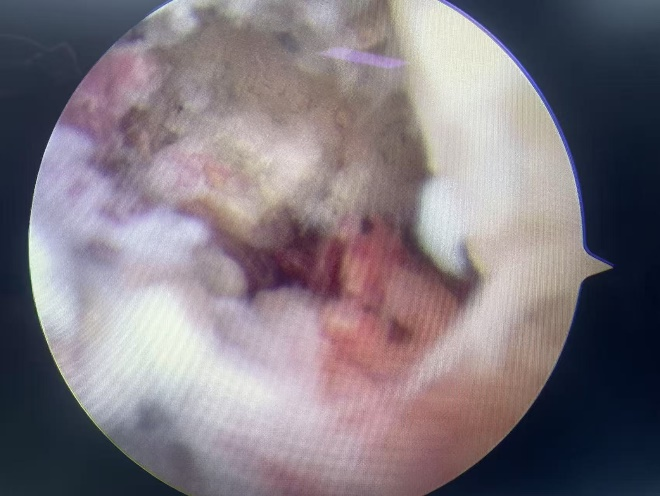

磁共振提示距腓前韧带断裂

关节镜观察断裂的距腓前韧带